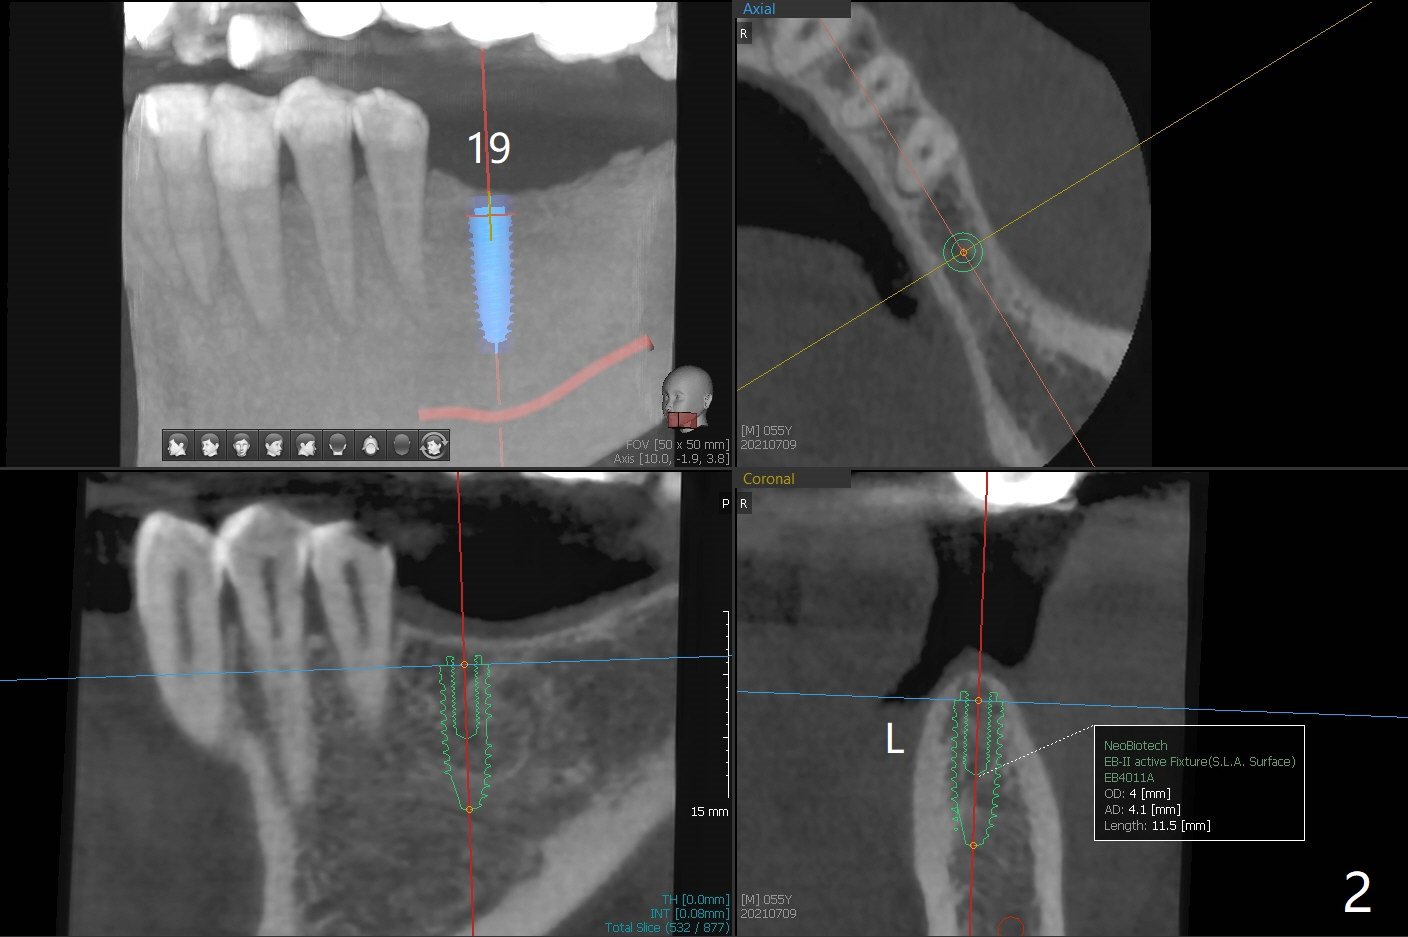

A 55-year-old man agrees to have implant(s) to be placed on the left side 4 years post #29 and 30 implantation. Recently the tooth #31 lost crown (Fig.1). Since the tooth #15 is supraerupted, an implant will be placed at #19 first. A 4 mm implant will be placed in the narrow ridge of #19 (Fig.2).